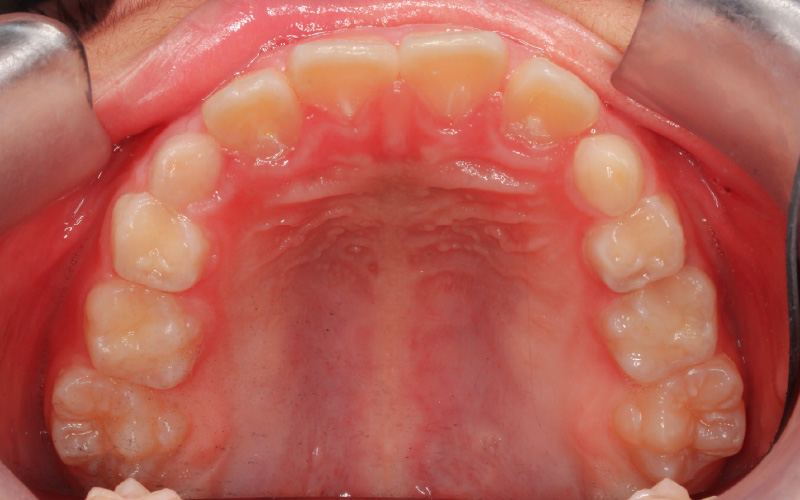

治療前

[11歳1か月]

顔立ちと咬み合せのために下顎の成長が必要と考え、まず顎関節の発育状態をチェックしました。その時重要な役割を果たすのがこの症例の場合MRIです。円板転位は初期で、2次軟骨も成長スパート直前の状態であるとわかりました。

まず歯の配列のみを考えている装置を外し、歯を並べる準備ができるまで、咬み合せを安定させるスタビライゼーションスプリントを1日12〜15時間程(主に夜間)装着してもらい、定期的にチェックして下顎の成長を観察しました。